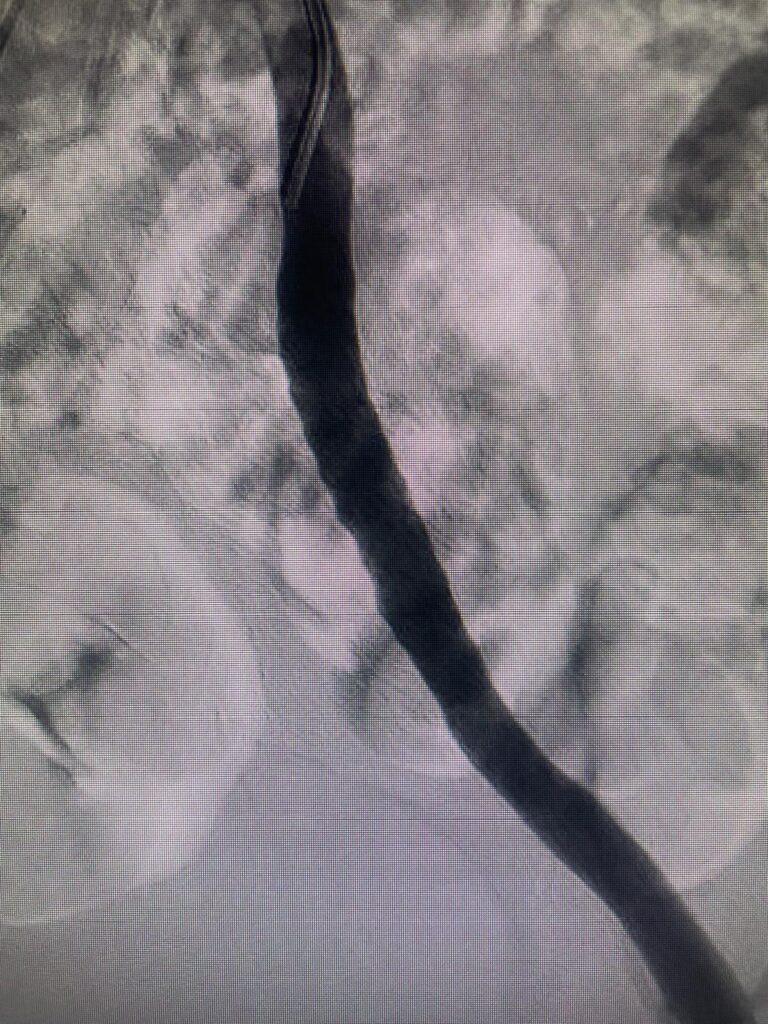

Durante la mesa, se revisaron los avances más recientes en el diagnóstico, tratamiento y manejo integral de la insuficiencia venosa crónica, destacando la importancia de la colaboración interdisciplinar y la actualización constante en el abordaje de esta enfermedad.